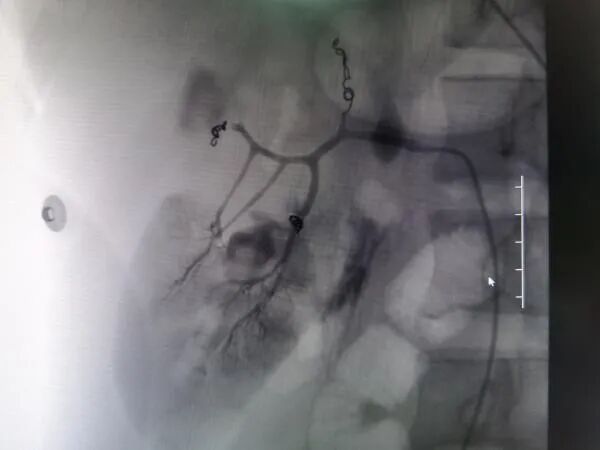

术前DSA造影图,红色箭头指示为出血点

救治方案明确后,患者立即被推入了手术室,在邓文军总监的指挥下,一场惊心动魄、紧张有序的手术开始了。各专科主任严阵以待,在院待命,随时做好开腹手术准备。介入手术由影像中心副主任兼介入组组长吴继雄主任医师亲自主刀,手术过程顺利,术中造影找到右肾脏有几处明显的活动性出血点,肝脏也有两处活动性出血点,给予及时栓塞止血后,再次造影无明显出血。整个手术仅约一个小时,刀口仅针眼大小,术中病人情况稳定,失血量不到10ml,患者成功脱离生命危险,术后被送入ICU密切观察诊治。病情平稳后转入普通病房,经过后续治疗目前该患者已经平安出院,出院时状态良好已经能自行走路。